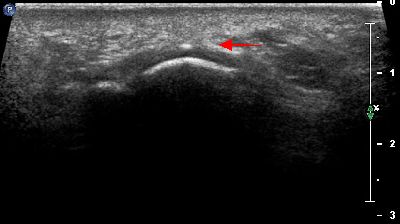

Calcificazione intra articolare (img. 01) Calcificazione intra articolare 01